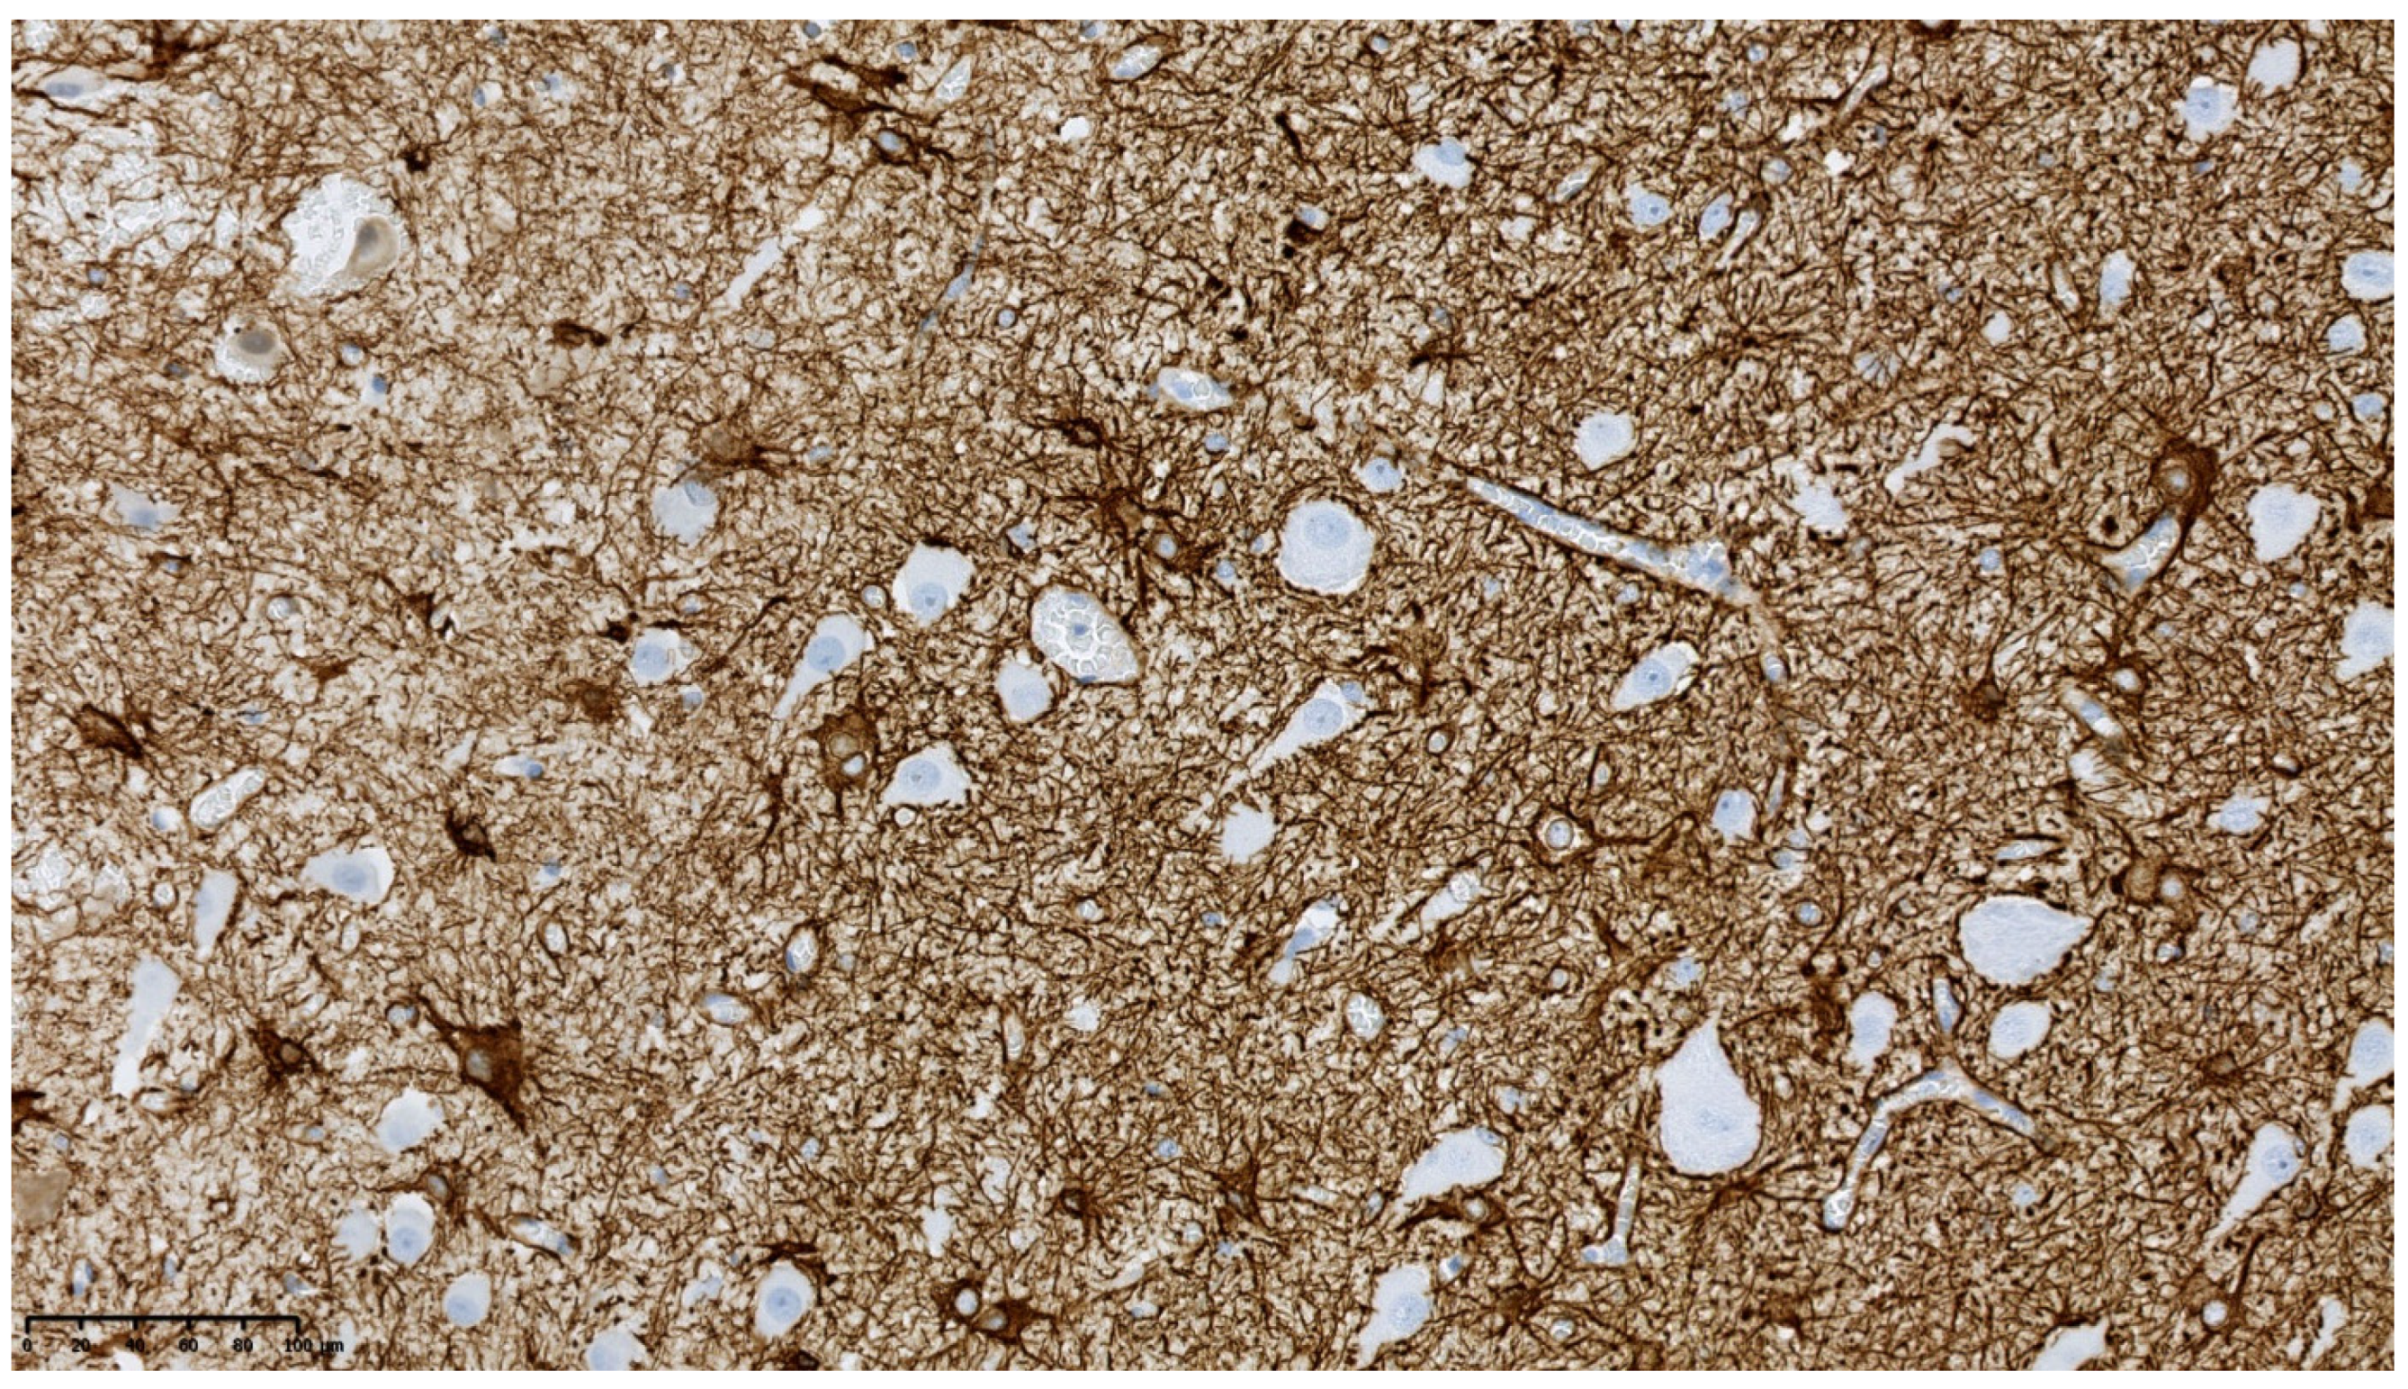

3.1. Clinical and Pathology Report